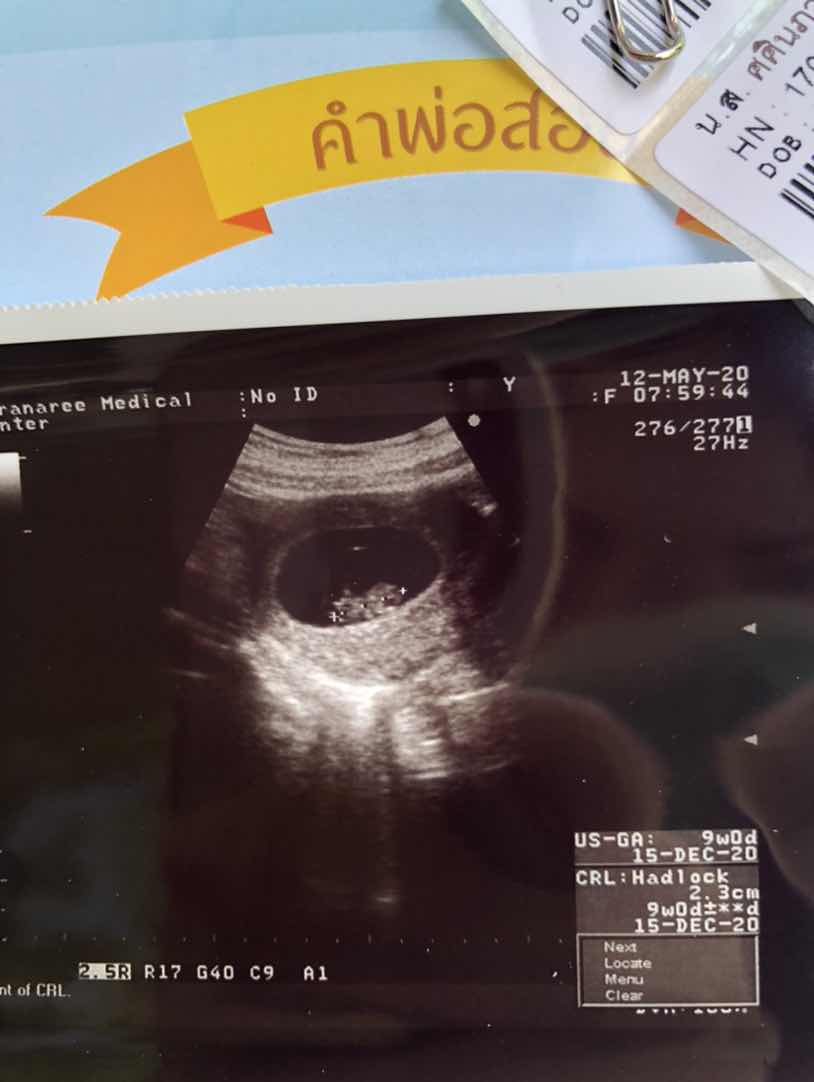

15 ธันวา คะ 😍